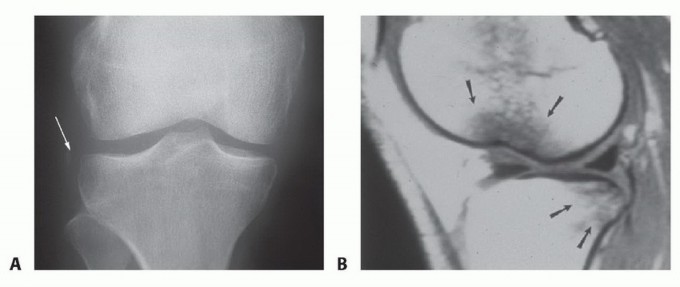

DEFINITION Tibial spine fractures are bony avulsions of the anterior cruciate ligament (ACL) from its attachm…